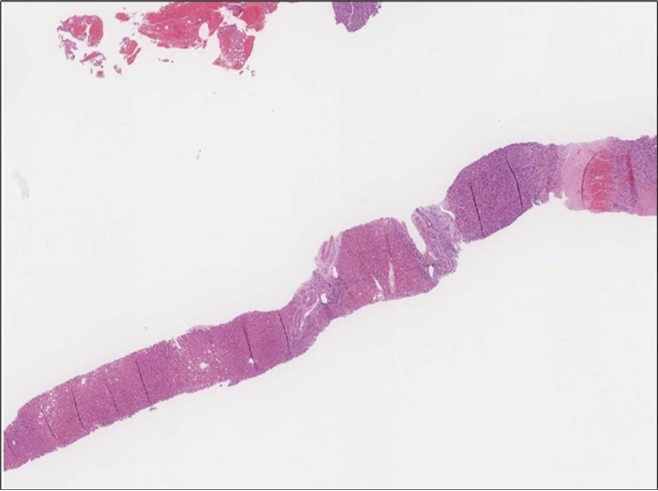

When diagnosing thyroid swelling, imaging studies have been helpful in differentiating malignant from benign tumors with US being used as an initial evaluation tool when assessing thyroid nodules. Tumors are categorized based on composition, echogenicity, shape, margin and echogenic foci into added scores determined by the TI-RADS system, which determines the need for FNA 13. Other imaging modalities include MRI and CT. However; radiological assessment does not distinguish between the types of thyroid cancer, and therefore FNA and biopsy are of crucial importance 3, 6. On a pathologic sample, LMS appears as spindled eosinophilic cells with elongated blunt-ended or cigar-like nuclei arranged in fascicles 2, 7 (Figure 1, Figure 2, Figure 3). Despite the unique microscopic morphology, LMS cannot be distinguished from other spindle cell tumors such as spindle cell variant of medullary thyroid cancer, anaplastic thyroid

Figure 1.Left thyroid Low power of the thyroid gland showing complete replacement of the thyroid by the neoplastic cells (H&E, ×4).